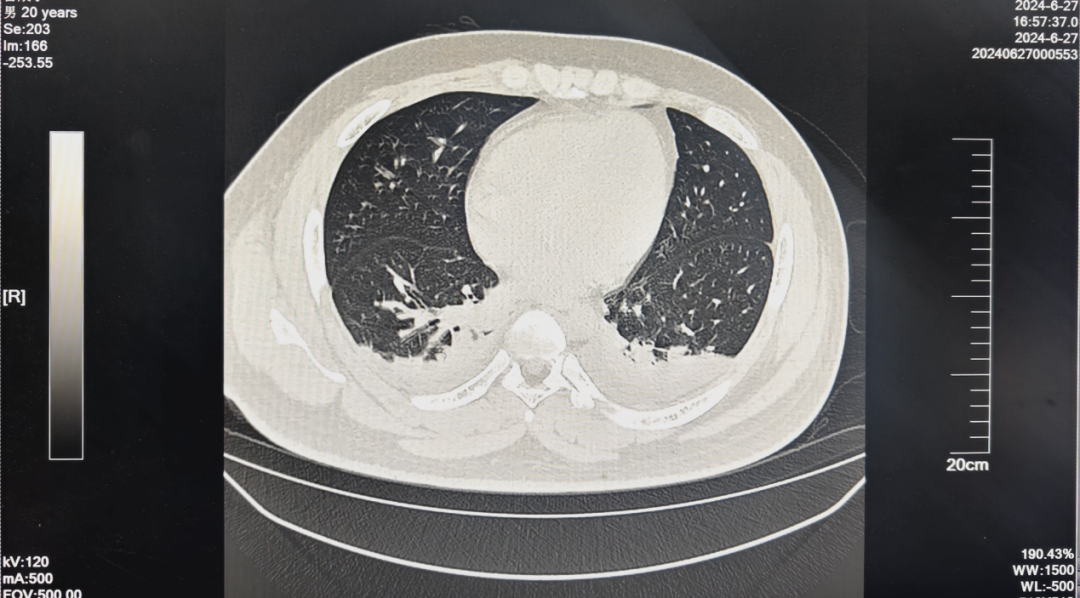

中毒后数日,在百草枯炎症风暴下,患者出现肝脏、肾脏等多脏器功能严重损伤。患者双肺出现了明显渗出,胸腔积液,导致双肺膨胀不全,具体表现为患者呼吸困难,血氧饱和度仅维持在90%,病情逐渐加重进展。